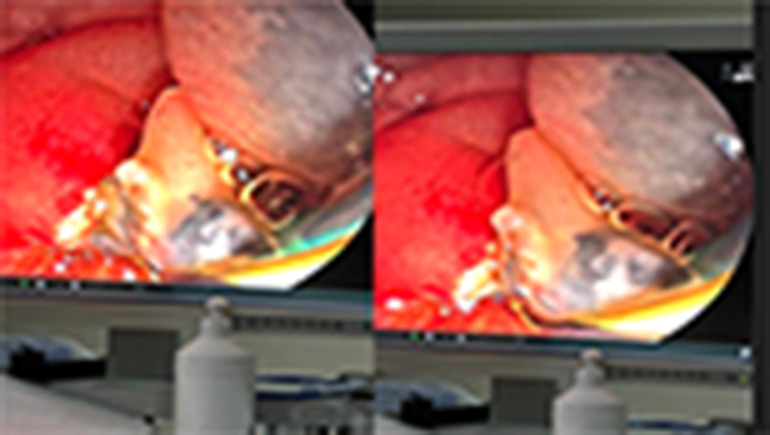

This article discusses Fasciola hepatica infection, a zoonotic parasite that lives in the liver bile ducts. A 31-year-old female patient was diagnosed with symptoms such as nausea, increased liver enzymes, and right upper quadrant pain for about a year. The parasite was detected in the common bile duct by Endoscopic Ultrasound (EUS) and removed by Endoscopic Retrograde Cholangio Pancreatography (ERCP). Treatment was performed with 10 mg/kg triclabendazole. Eosinophilia, abdominal pain, and dietary history are important clues in the diagnosis of infection. Imaging methods, especially EUS, play a critical role in diagnosis. With this method, parasites can be seen as mobile hyperechogenic structures. If untreated, parasites can survive in their hosts for many years, therefore early diagnosis and treatment are important in preventing complications. It is recommended to monitor the eosinophil levels and serological test results of patients after treatment. As a result, EUS is a very valuable diagnostic tool in suspected cases.

Abstract Image